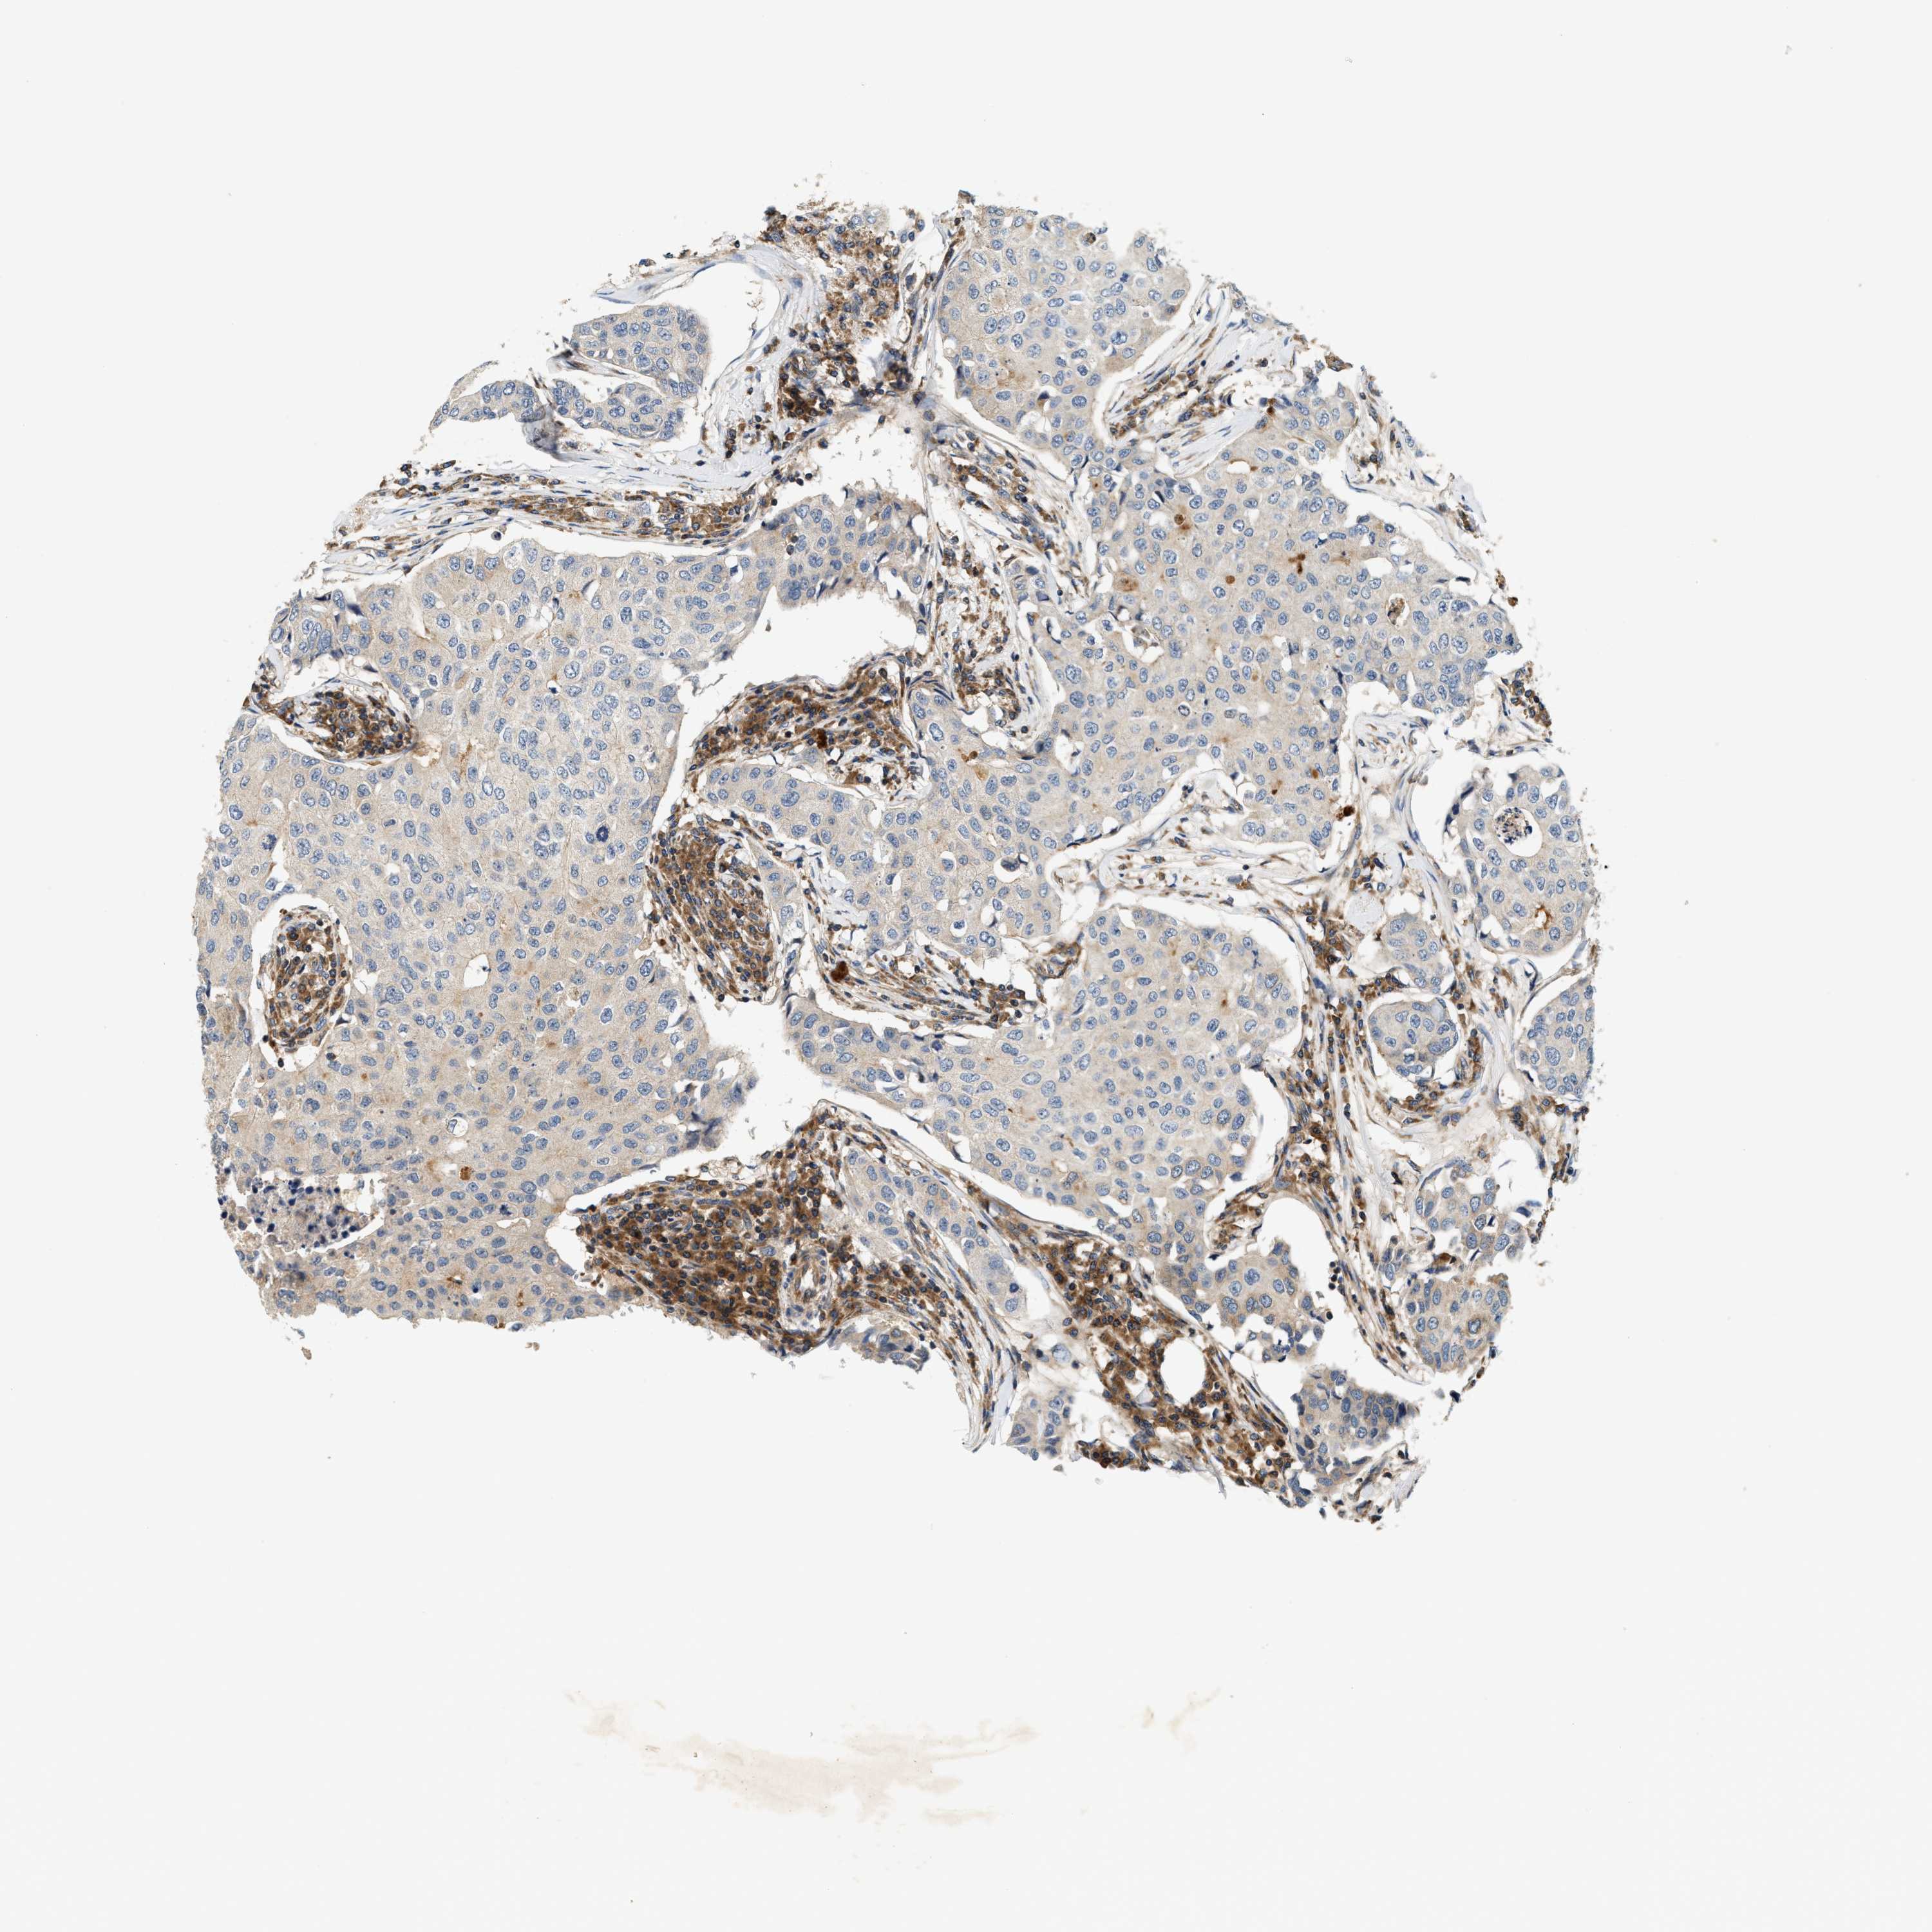

CANCER BREAST CANCER Show tissue menu

BRCA TCGA BRCA VALIDATION PROTEIN EXPRESSION

Breast cancer

Human cancer